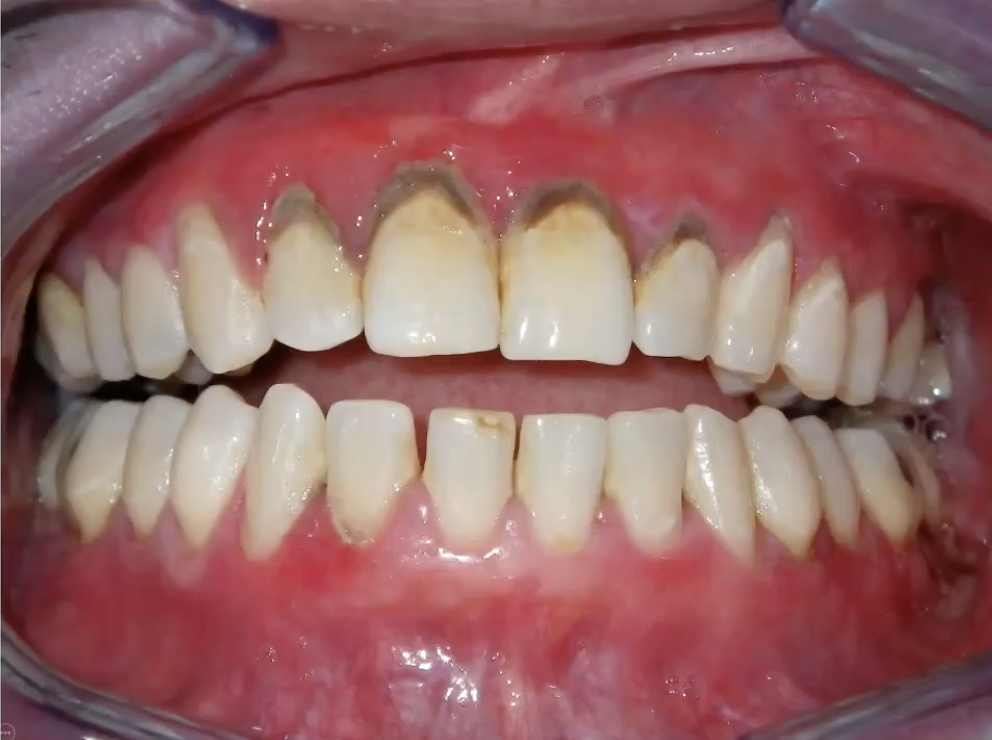

Desquamative Gingivitis

what condition?

• Diffuse, markedly erythematous gingiva

• Generally involves attached tissues